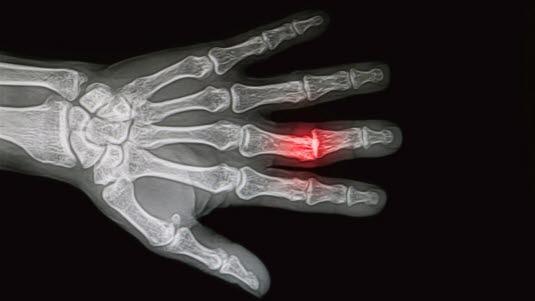

Beinbrudd påvises eller mistenkes når man på røntgen finner tydelige eller mindre tydelige bruddlinjer. Noen ganger kan det ses som en innpressing eller utbuling av beinet.

Beinbrudd påvises eller mistenkes når man på røntgen finner tydelige eller mindre tydelige bruddlinjer. Noen ganger kan det ses som en innpressing eller utbuling av beinet. Mistanken kan også vekkes når man finner tydelig hevelse i bløtvevet rundt beinet. Noen brudd kan være vanskelig å oppdage når skaden er fersk, men de vises tydeligere når tilhelingen er startet (etter noen uker).

Ofte står et brudd skjevt slik at beinpipene står skjevt i forhold til hverandre (se figur), ja, noen ganger kan de ha glidd forbi hverandre. Da må legen dra bruddendene fra hverandre før de presses på plass (reponeres). Legen er avhengig av å sammenligne bilder før og etter reposisjonen for å forsikre seg om at bruddet vil kunne gro riktig i den posisjonen det står. I oppfølgingen av et beinbrudd blir det også tatt bilder for å kontrollere at bruddet gror og at det ikke oppstår komplikasjoner av noe slag.